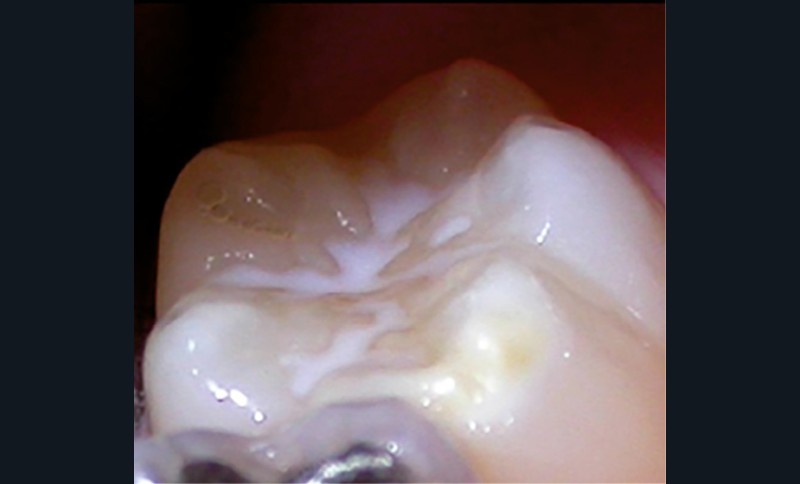

Cliniquement, les dents présentent des colorations blanches ou brunes opaques sur une partie ou sur toute la surface de la dent. Cette atteinte peut être légère (émail blanc, opaque), modérée (coloration jaune, brune, surface crayeuse et effondrement postéruptif de l’email) ou sévère (atteintes associées à des pertes de substances importantes) (fig. 1)

.